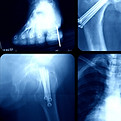

What is an extremity X-ray and what is it used for?

Extremity X-ray is a study that uses digital X-rays to obtain clear images of bones, joints, and nearby tissues in the hands, wrist, arm, foot, ankle, knee, femur, and shoulder.

It is used to diagnose fractures, dislocations, deformities, arthritis, bone infections, and to monitor orthopedic or post-surgical treatments.

Types and projections of Extremity X-rays

(hands, wrist, arm, foot, ankle, knee, femur and shoulder.)

Depending on the area, different views can be requested: